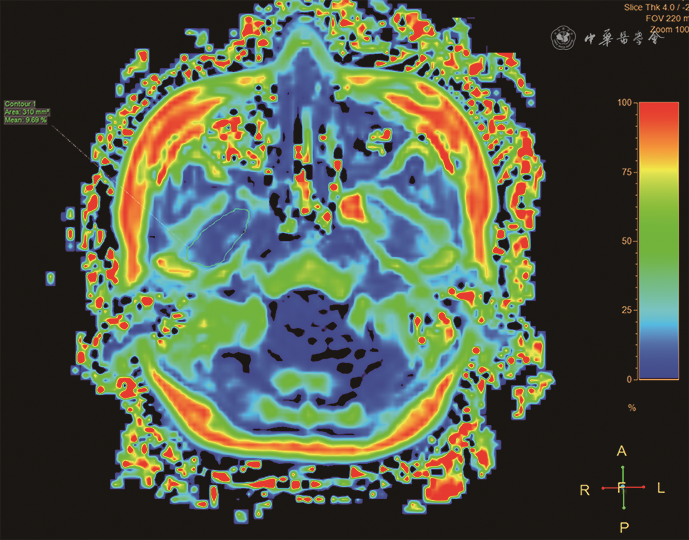

常规PDWI图像可观察翼外肌脂肪浸润,但不易评估微量的脂肪浸润。T1加权Dixon 序列(T1 weighted Dixon sequence)是基于化学位移进行水脂分离的一种磁共振成像技术,可发现肉眼不能识别的微量脂肪并做定量分析(图8)[23]。研究发现关节盘不可复性移位者的翼外肌脂肪成分(4.63%)较关节盘位置正常者(3.65%)轻度增高且具有统计学差异[23],因此,T1加权 Dixon序列可作为TMD进展的监测工具之一。